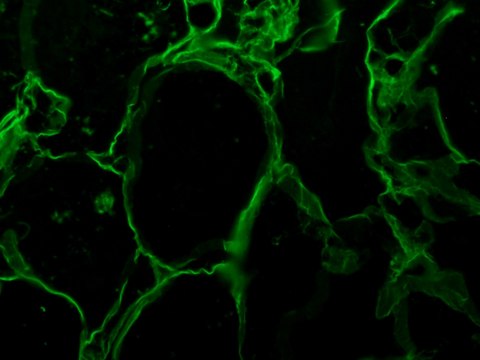

indirect immunofluorescence: 1:20 using formalin-fixed, paraffin-embedded sections of human tissue

The antibody localizes vimentin in normal and pathological tissue of mesenchymal derivation. The antibody shows wide cross-reactivity among mammalian species.